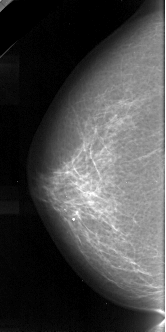

A_1050_1.LEFT_MLO

LEFT_MLO LINES 5236 PIXELS_PER_LINE 2311 BITS_PER_PIXEL 16 RESOLUTION 42 NON_OVERLAY